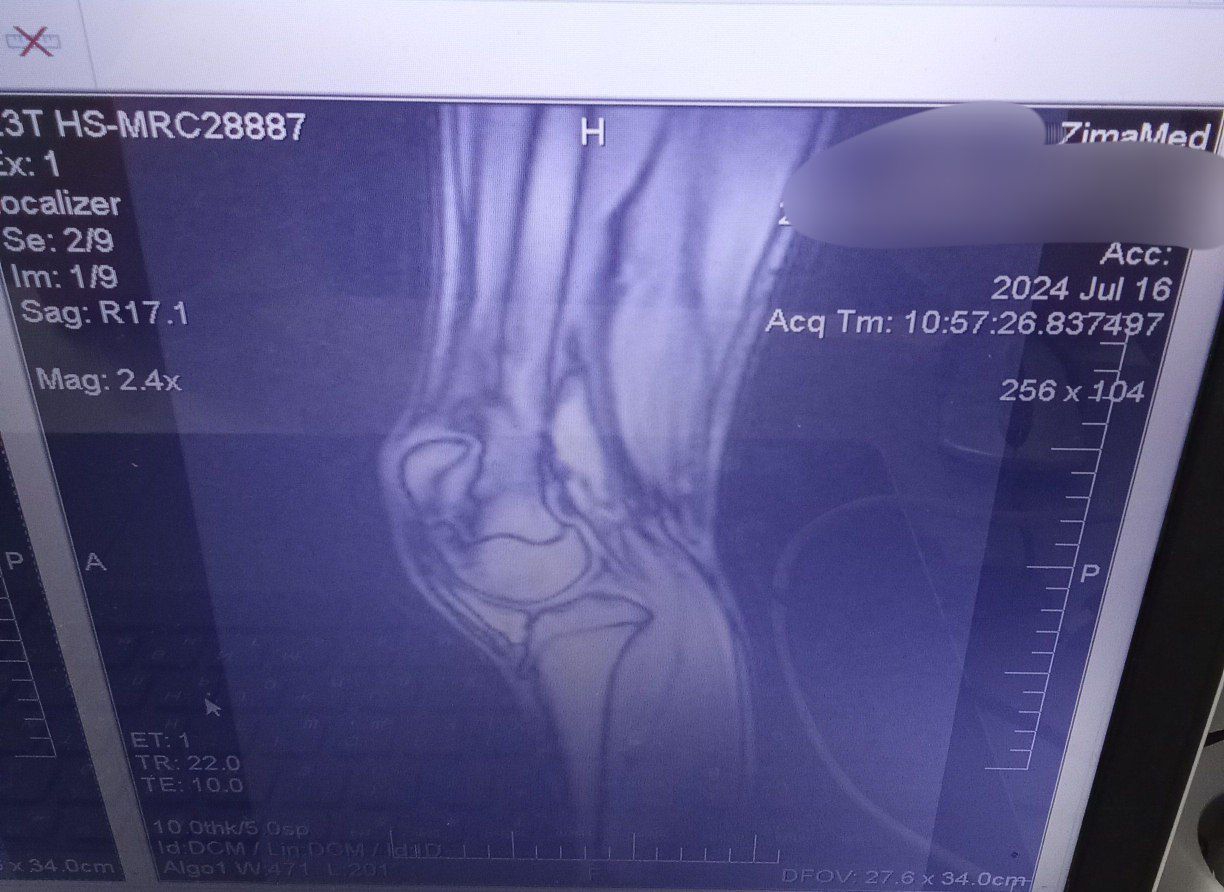

У меня такая же хуйня, но куда хуже, с рождения двухсторонняя дисплазия, в лет 11 началось проявление вальгусной деформации ног, спустя год стали вылетать надколенники (чашечки). С каждым годом это все ухудшалось и ухудшалось. Родители особо не торопились меня отводить к врачам, по этому к 14 я утратил способность нормально ходить (вечный страх что вот вот вылетит колено и я упаду) бегать я вовсе не могу, потому что надколенники сместились латерально кверху, по этому стабильность моих ног начинает качать уже от обычного ветра. Из за этого я не смог подписать контракт в 18 как и хотел, но начал процесс какого либо контакта с врачами и поиска решения проблемы без мам и пап. Сам выбивал справки и направления на бесплатные обследования. Спустя 4 месяцев сбора кучи обследования, пару рентгенов, пару мрт и одного торсиального кт. Мой хирург который взял меня под свое крыло, увидел во мне необычайно удивительный случай. Моментально уехал в Москву, там на какой то крутой конференции, он показал мои результаты обследований и видео подвижности моих ног другим врачам и как он передал, там все ахуели. Предложил мне относительно сложную операцию, типичная остеотомия, только пилить будут в двух местах бедро, в трёх большеберцовую кость и резекцию икры для предотвращения спазма нервов ну и замена связок на надколеннике. В итоге, мне остаётся букалаьно две недели до госпитализация и две недели и один день до операции. Я очень волнуюсь, потому что я забыл что уже такое бегать, что такое прыгать и ходить без страха вывихнуть колено.

IMG202507271253[...].jpg 97Кб, 577x1280

IMG202507271253[...].jpg 228Кб, 1280x960

IMG202507271253[...].jpg 195Кб, 960x1280

IMG202507271253[...].jpg 182Кб, 960x1280

IMG202507271253[...].jpg 183Кб, 1217x959

IMG202507271253[...].jpg 199Кб, 1224x892

IMG202410312014[...].jpg 25Кб, 299x781

IMG202507271253[...].jpg 126Кб, 1138x788